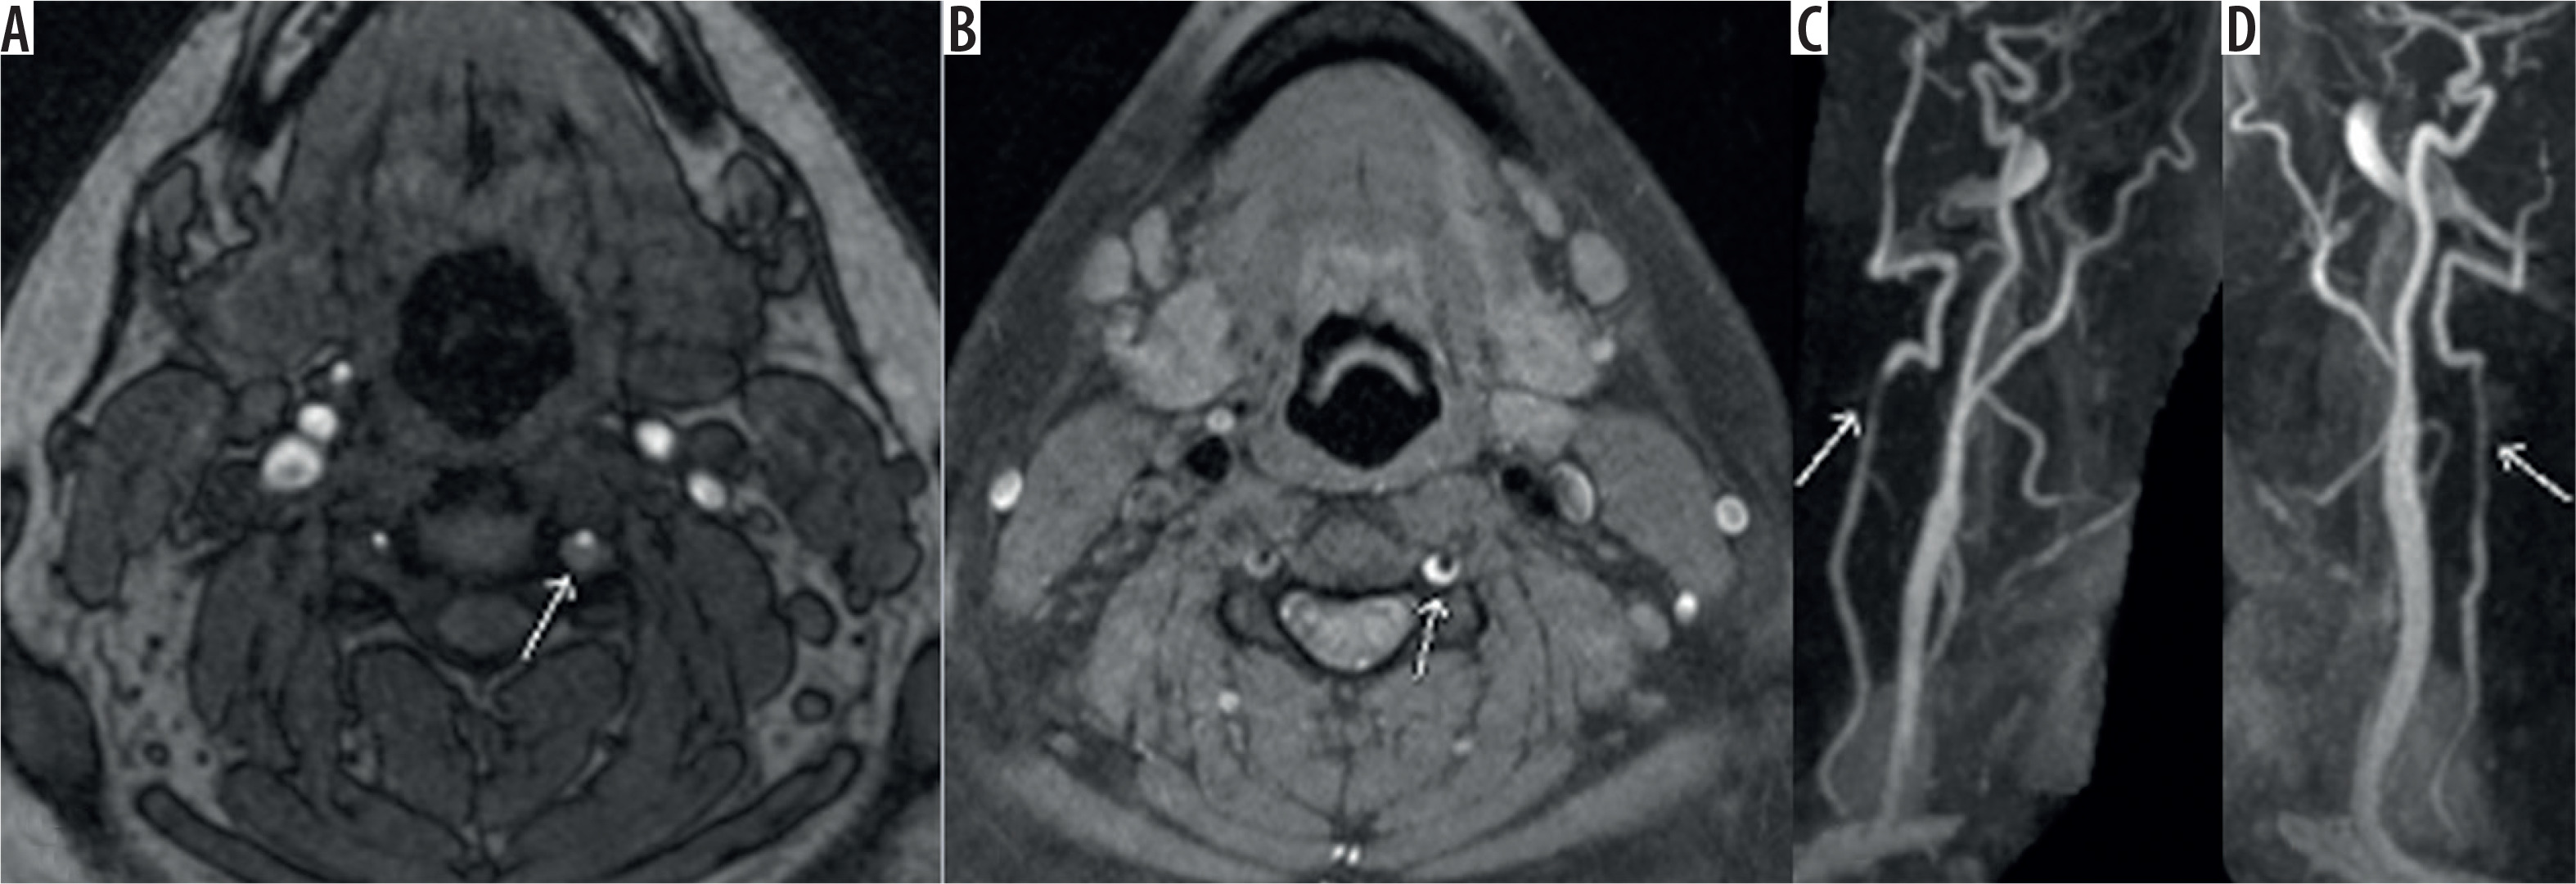

Figure 7

Axial time-of-flight magnetic resonance angiography image (A) showing intramural haematoma as seen by abnormal signal surrounding and narrowing the left vertebral artery flow signal (white arrow). T1 fat-saturated image (B) showing the T1 hyperintense signal consistent with intramural haematoma (white arrow) and the reformatted images showing luminal narrowing (C, D) (white arrow)